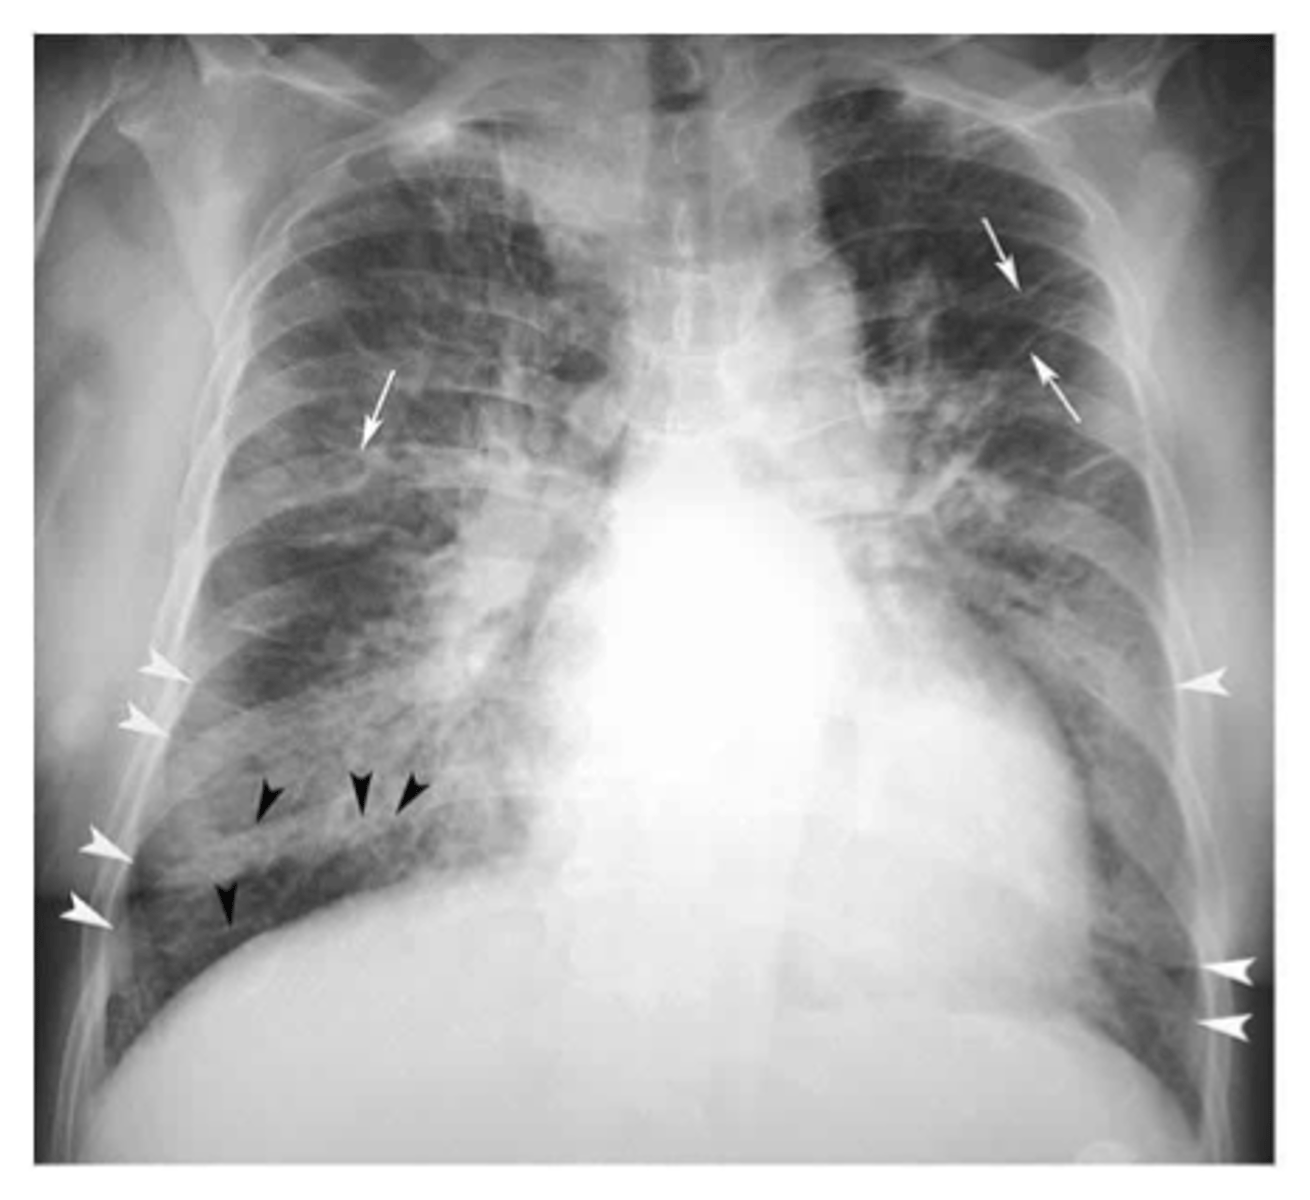

Flattening of hemidiaphragms

& blunting of costophrenic angles, Increased AP diameter (barrel chest), bullae or large air cavities indicates

hyperinflation

COPD/Emphysema

knowt flashcard image